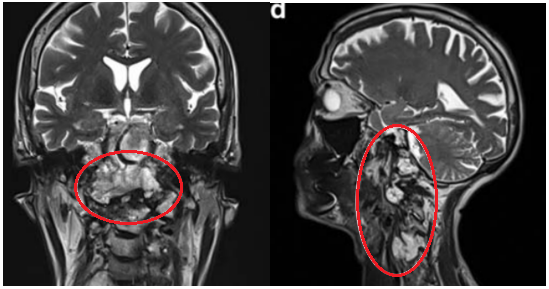

年轻女性因颈部疼痛就诊,MRI发现颅颈交界区脊索瘤,伴骨质破坏和硬膜内延伸,累及双侧椎动脉。

治疗策略:采用内镜辅助的前外侧入路顺利切除肿瘤,术后几天行枕颈融合术确保稳定性。